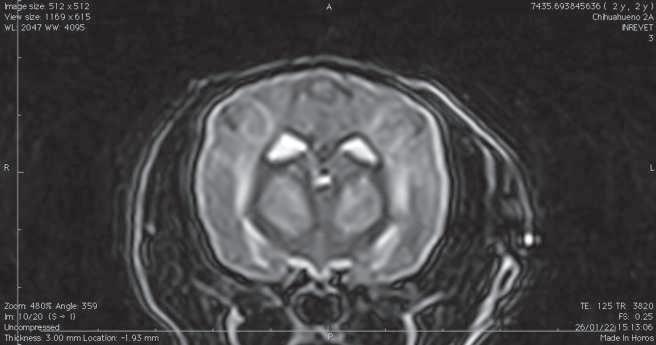

Figura 1. (A y C) Imágenes ponderadas en T2W. (B y D) FLAIR con lesiones hiperintensas en múltiples regiones encefálicas asociados a focos de edema con mayor evidencia en núcleos basales y tálamo (A, B) y lóbulos parietales y temporales (C y D).

Figura 2. Imágenes ponderadas en T2W (A, C) y FLAIR (B, D) en las cuales se aprecia una disminución en las lesiones hiperintensas descritas en la figura 1.

Conbasealosresultadosderesonancia magnética (Figura 1), raza y hallazgos neurológicos los pacientes fueron diagnosticados con enfermedad inflamatoria cerebral (Meningoencefalitis de origen desconocido) e iniciaron con una terapia basadaenStee2020,10 conlacombinación decitarabina(Cytosar-U®Pfizer500mg) a dosis de 100/m2 y prednisona a dosis de 1 mg/kg iniciales por 4 semanas (dosis reducción a 36 semanas), para posteriormente evaluar la evolución clínica del paciente y por imagen con las mismas indicaciones de resonancia previamente descritas.

En el presente estudio 5 de 6 pacientes mostraronunamejoracínicasignificativa, enunpaciente(Shih-tzu)elcualingresóen estatus epiléptico no presentó más crisis convulsivas ni se han reportado hasta el momento, el estado mental de los 6 pacientes mejoró de forma significativa, sólounpaciente(Yorkshire)conimágenes por resonancia magnética con herniación subfalcina continuó con giros, los déficits propioceptivos continuaron en 2 de 6 pacientes (Cuadro 3). En las imágenes por resonancia magnética posterior a las 4 semanas iniciado el tratamiento se vio unadisminucióndeledemareportadoque va desde el 85% hasta 50% (Figura 2).

El propósito del presente estudio fue determinar la relación entre la respuesta clínica y la evaluación de las imágenes por resonancia magnética en estudios seriados usando un protocolo de tratamiento basado zen las regiones con hiperintensidad enT2Wfue notoria en la mayoríadeloscasosdescritos.Sepresentó una predilección en hembras (4 de 6) como varios estudios han reportado.1,7,11 Dos casos se presentaron con convulsiones agudas sintomáticas, uno de ellos en estatus epiléptico, Kaczmarska, et al., reportaron una prevalencia del 50% de convulsiones,5 en algunos otros reportes varía del 23% al 37.5%.12,13 Se ha informado que la RM tiene una sensibilidad

del 94.4% y una especificidad del 95.5% para detectar una anomalía cerebral, con un rendimiento similarmente alto para clasificar enfermedades neoplásicas e inflamatorias,14 aunque actualmente no hay información disponible sobre el uso deresonanciamagnéticaparadiferenciar entrecasosconfirmadoshistopatológicamente de MEG, MEN, LEN.